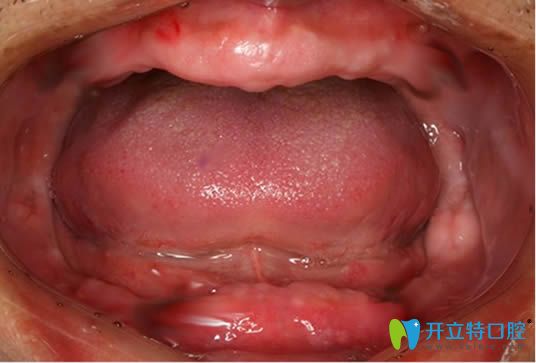

全口吸附性義齒主要是根據(jù)個(gè)人牙槽骨條件,由醫(yī)生精細(xì)取模和后期技師的制作,才能使義齒達(dá)到充分的邊緣封閉,和牙床產(chǎn)生牢固的吸附力,下文就有講解,并附bps生物吸附性義齒的收費(fèi)價(jià)格